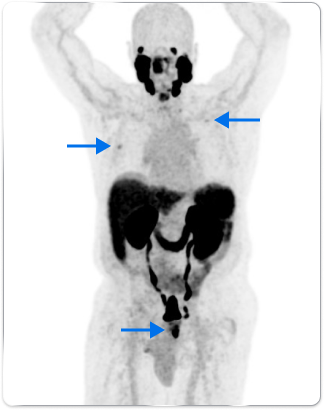

High-risk patient with newly diagnosed prostate cancer

Age

72

PSA (ng/mL)

5.1

Gleason Score

4 + 4

PYLARIFY prompted treatment change from prostatectomy to systemic therapy, thereby avoiding undertreatment